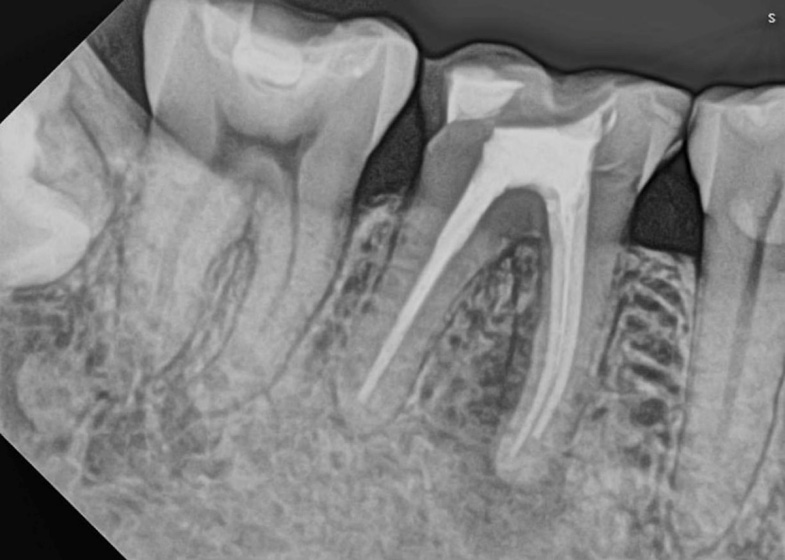

This patient arrived at the office reporting pain upon vertical percussion and during chewing.

Radiographic examination revealed a pepiapical lesion in the mesial root.

Initial Xray

Immediate postoperative Xray